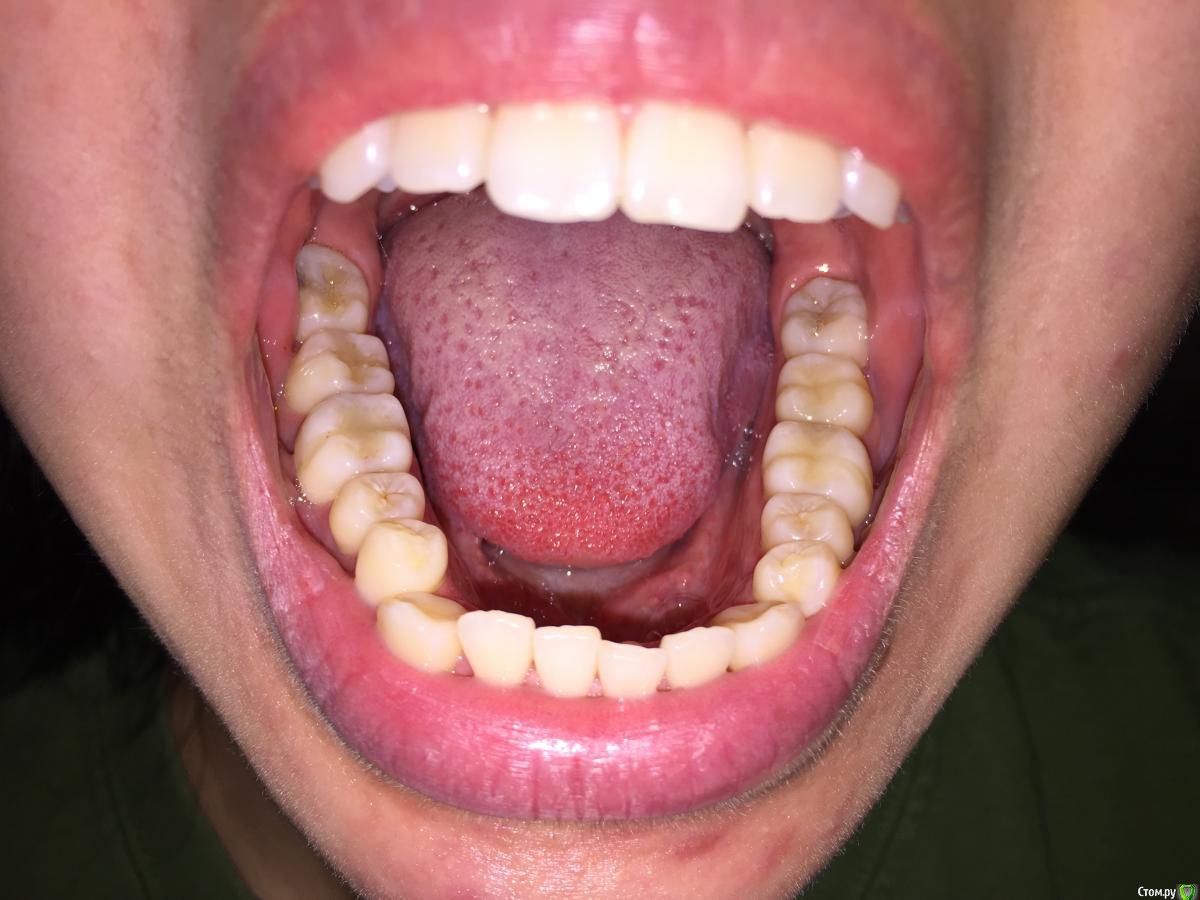

Помогите разобраться, мнения коллег разошлись.

Пациентке 21год, беспокоит 43 выдвинут вперёд, рецессия Десны у 14, 24.

1. Поставить брекеты, чтоб выровнять нижний ряд.

2. Удалить 48 и 28 и затем поставить брекеты

3. Ничего не делать, оставить так как есть.